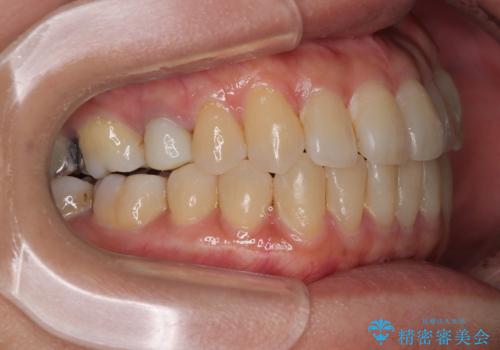

受け口と八重歯を改善 インビザライン矯正治療

- 前歯のデコボコや八重歯を治したいとのことで来院された患者様です。

受け口傾向の骨格であり、前歯はクロスバイトまたは切端咬合となっており、下顎を中心に歯列全体の後方移動を行い、IPR(歯と歯の間を削る)によってデコボコが解消するように設計し、インビザラインにより治療を行うこととしました。

受け口傾向のインビザライン矯正は比較的治療を行いやすいため、きれいに仕上げることができました。舌の突出癖が顕著であったため、改善のためのトレーニングをしっかりと行っていただきました。